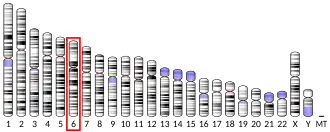

Vascular endothelial growth factor A (VEGF-A) is a protein that in humans is encoded by the VEGFA gene.[5]

During embryonic development angiogenesis is initiated as mesoderm mesenchyme cells are specified to differentiate into angioblasts, expressing the Vascular Endothelial Growth Factor Receptor (VEGFR-2). As embryonic tissue utilizes more oxygen than it receives from diffusion, it becomes hypoxic. These cells will secrete the signaling molecule vascular endothelial factor A (VEGFA) which will recruit the angioblasts expressing its partnering receptor to the site of future angiogenesis. The angioblasts will create scaffolding structures that form the primary capillary plexus from where the local vasculature system will develop. Disruption of this gene in mice resulted in abnormal embryonic blood vessel formation, resulting in underdeveloped vascular structures. This gene is also upregulated in many tumors and its expression is correlated with tumor development and is a target in many developing cancer therapeutics. Elevated levels of this protein are found in patients with POEMS syndrome, also known as Crow-Fukase syndrome which is a hemangioblastic proliferative disorder. Allelic variants of this gene have been associated with microvascular complications of diabetes 1 and atherosclerosis.

- ^ Mattei MG, Borg JP, Rosnet O, Marmé D, Birnbaum D (February 1996). "Assignment of vascular endothelial growth factor (VEGF) and placenta growth factor (PLGF) genes to human chromosome 6p12-p21 and 14q24-q31 regions, respectively". Genomics. 32 (1): 168–169. doi:10.1006/geno.1996.0098. PMID 8786112.